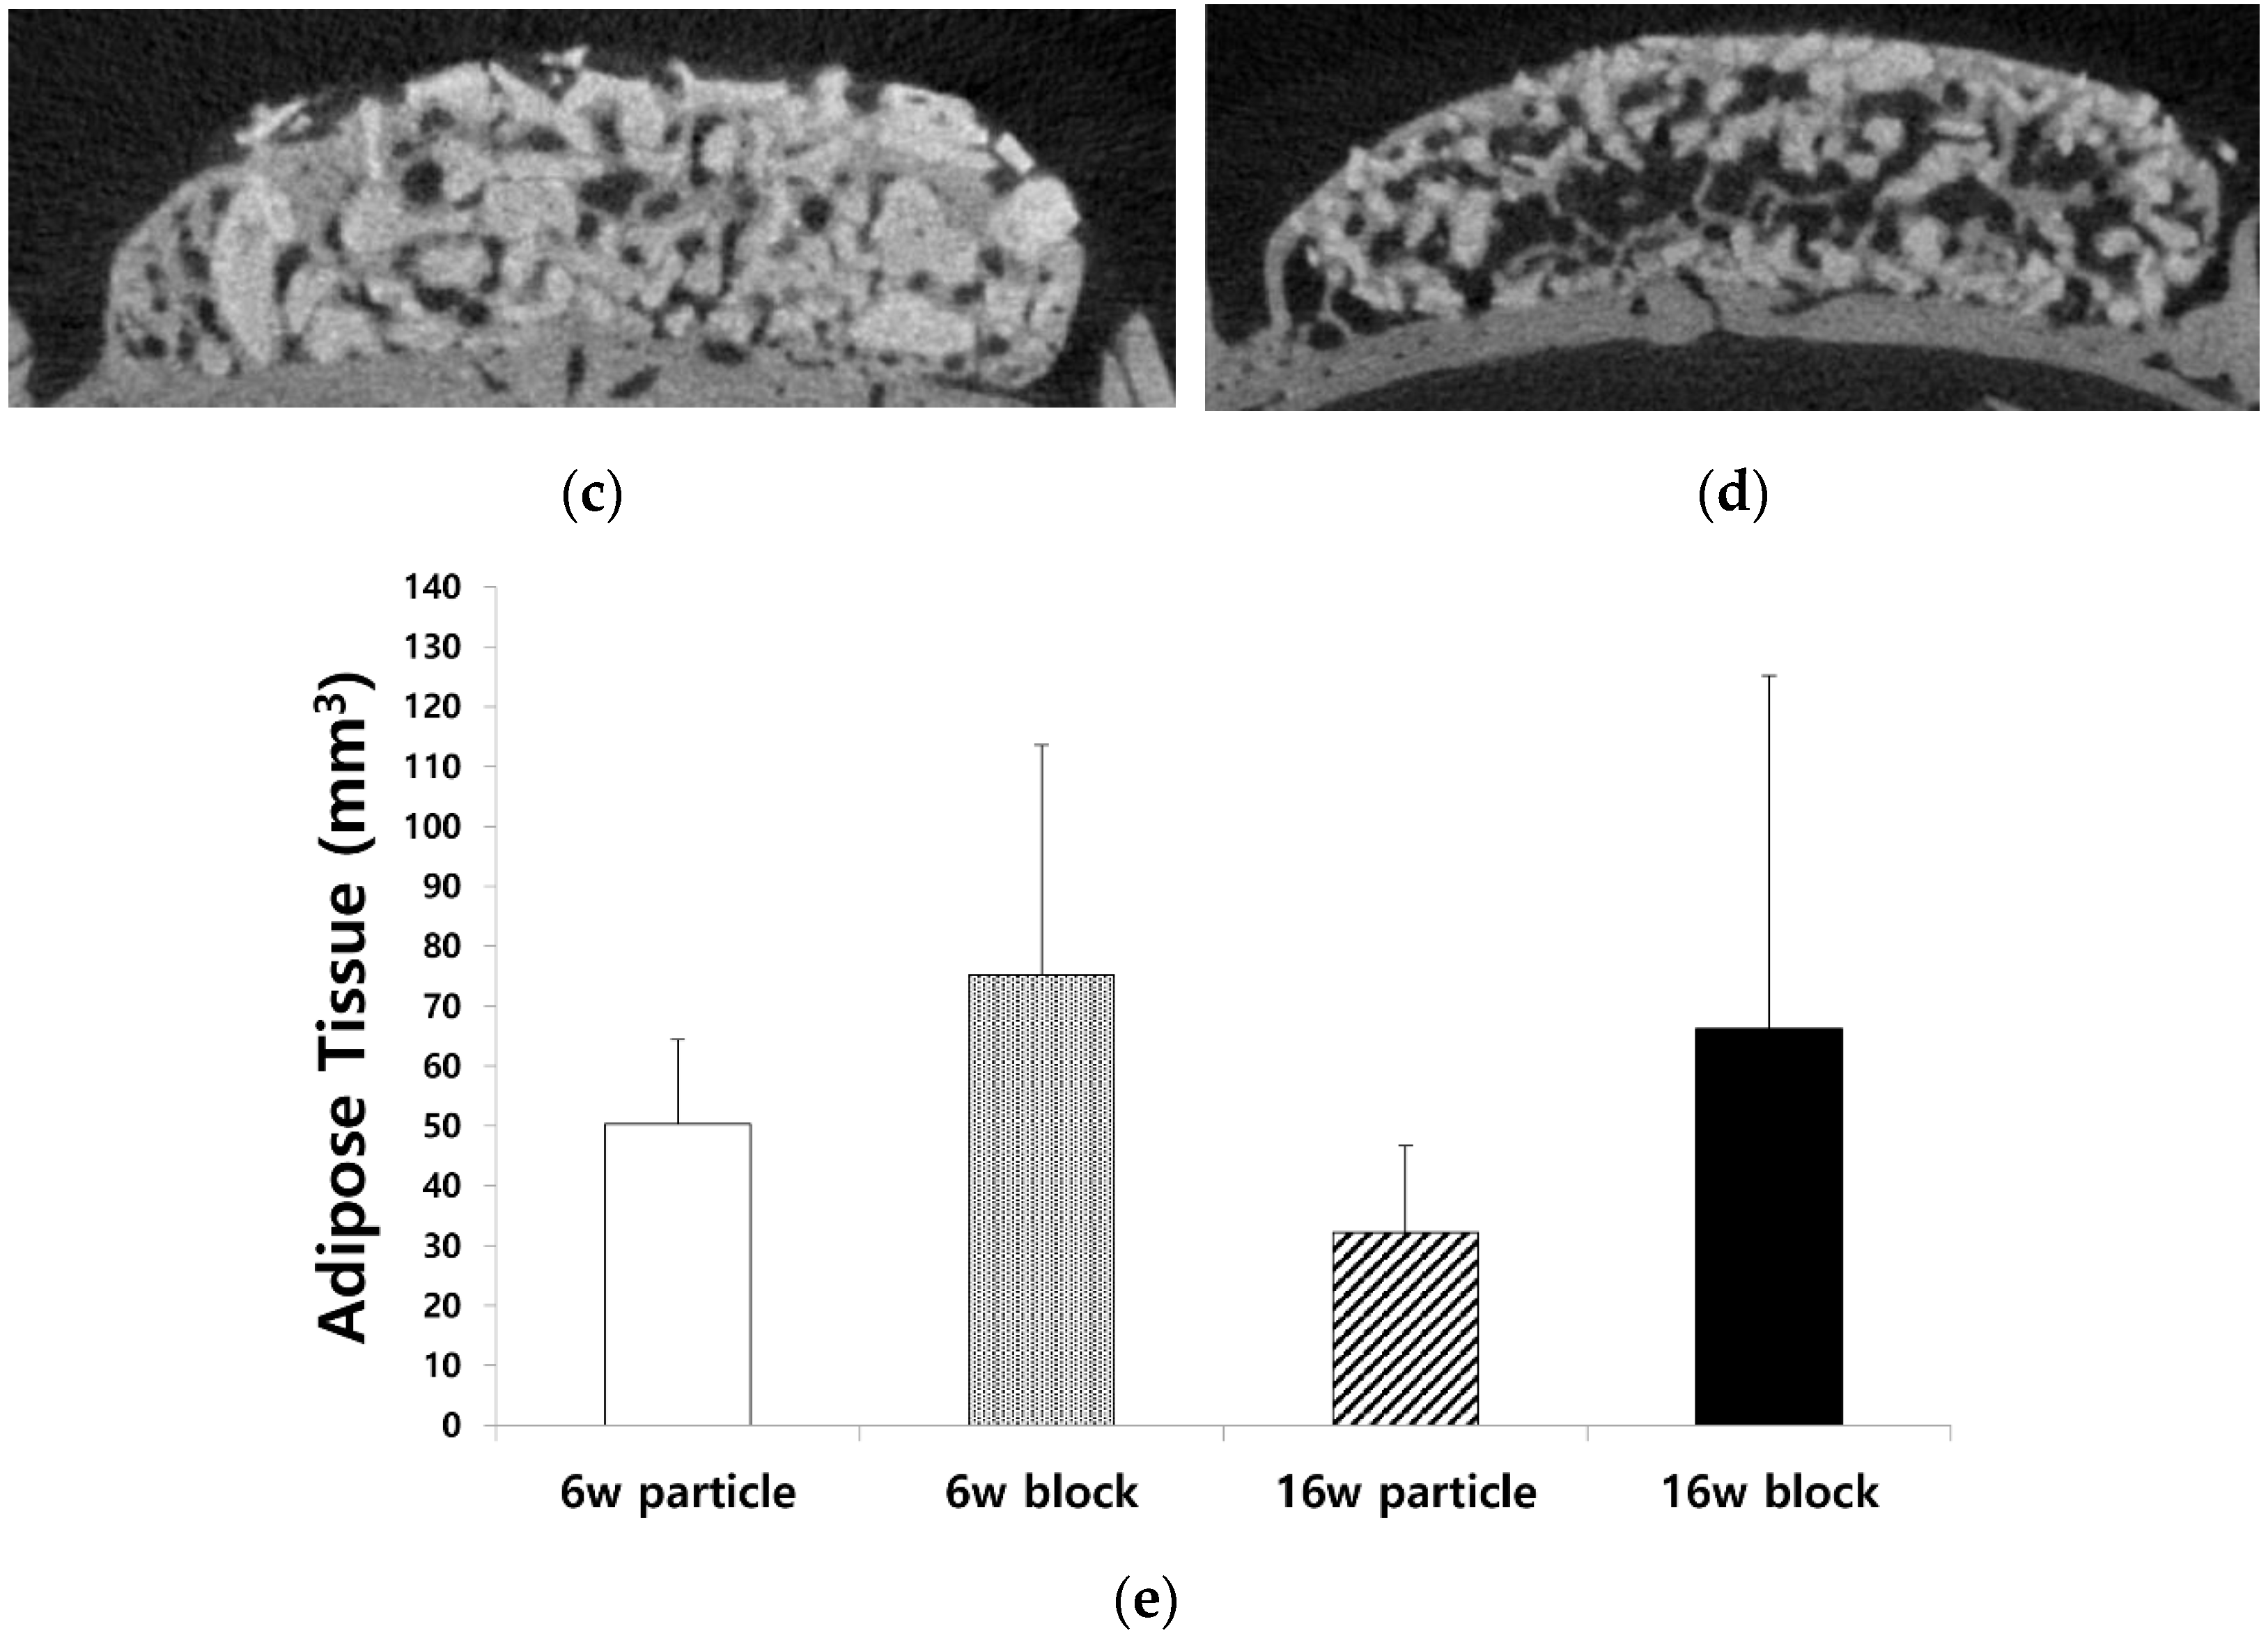

3.2. Changes in Adipose Tissue in the Newly Formed Bone